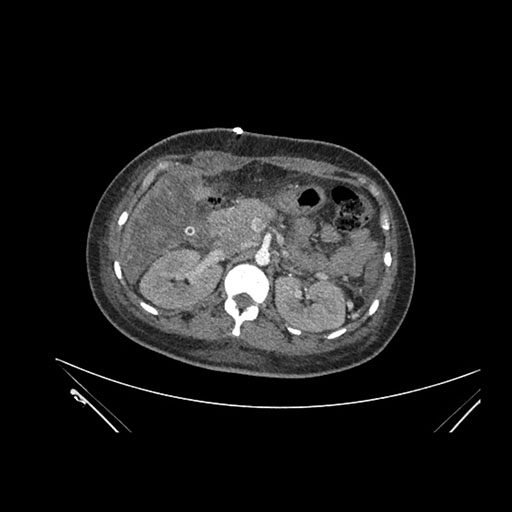

Axial Arterial

Axial Venous